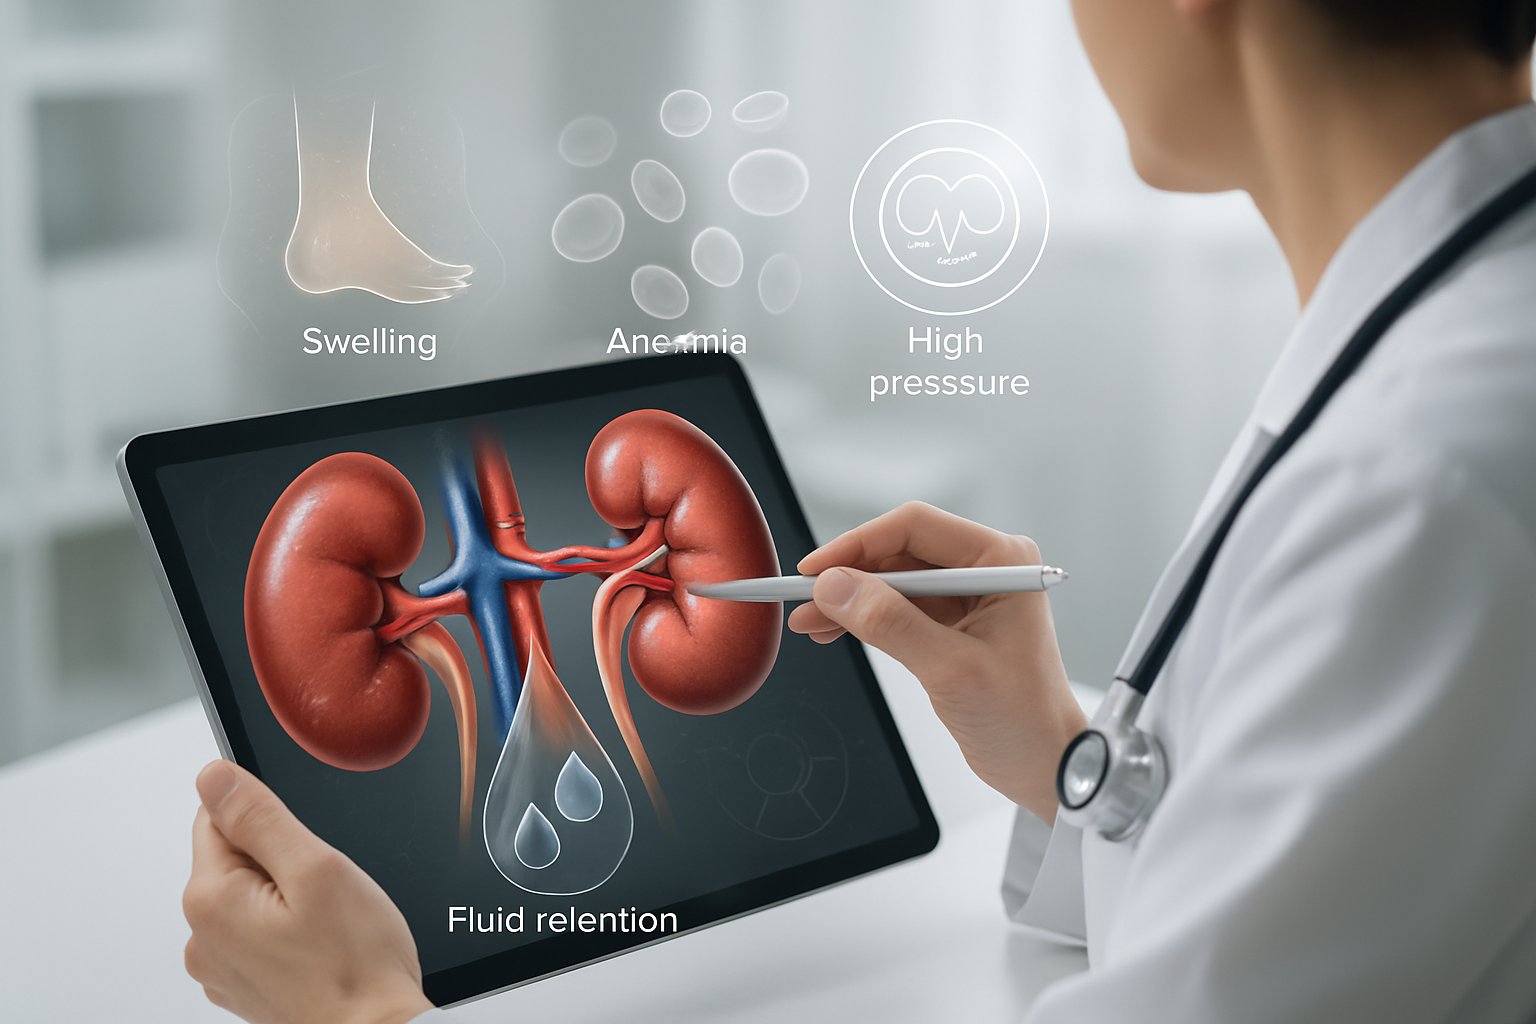

Signs and Symptoms of Kidney Failure

Kidney failure develops gradually, with symptoms often appearing only after significant damage has occurred. The most common early warning signs include extreme tiredness, swelling, and changes in urination[1], while advanced stages bring more severe complications affecting multiple body systems.

Fatigue ranks among the earliest indicators of kidney problems. Healthy kidneys produce a hormone called erythropoietin that signals the body to make red blood cells[6]. When kidney function declines, red blood cell production drops, leading to anemia and persistent tiredness.

Severe swelling (edema) becomes more noticeable, particularly around the ankles, hands, and face. Fluid retention can cause rapid weight gain and difficulty fitting into shoes or clothing.

Common Complications of Kidney Failure

When kidneys fail, complications affect many body systems[7] because these organs control fluid balance, blood pressure, and waste removal. The body struggles with dangerous mineral imbalances, heart problems from fluid buildup, and toxic waste accumulation.

Fluid retention causes swelling in the legs, ankles, and around the eyes. Some people gain weight quickly from excess fluid buildup.

Kidney failure puts severe stress on the heart and blood vessels. Heart disease becomes a major risk[8] for people with failed kidneys.

High blood pressure worsens as the kidneys cannot control fluid balance. Blood pressure often becomes hard to control even with multiple medications. This increases the risk of stroke and heart failure.

Anemia develops because kidneys make a hormone called erythropoietin that tells the body to produce red blood cells. Without this hormone, red blood cell counts drop dangerously low. Patients feel tired, weak, and short of breath.

The combination of fluid retention and anemia forces the heart to work much harder. This can lead to heart failure, where the heart cannot pump blood effectively throughout the body.